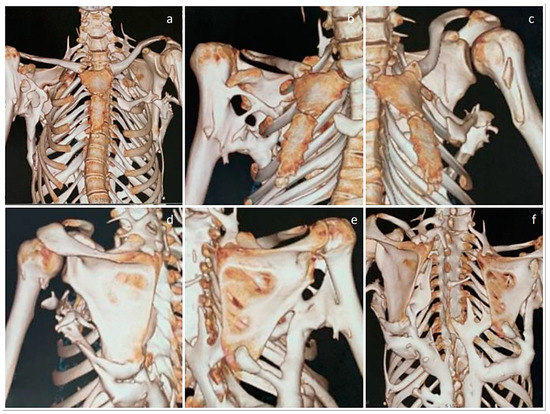

Figure 2. Whole-spine CT scans, both coronal and sagittal sections. (ad) Sections clearly show the thoracolumbar scoliosis, along with fused cervical disc spaces and posterior elements, with only the discs above and below C7 appearing to be spared. (c) Sagittal section shows the fusion of thoracic disc spaces and the thoracolumbar posterior elements. (c,d) The heterotopic bone involving the posterior muscles are also seen clearly in the sagittal views.